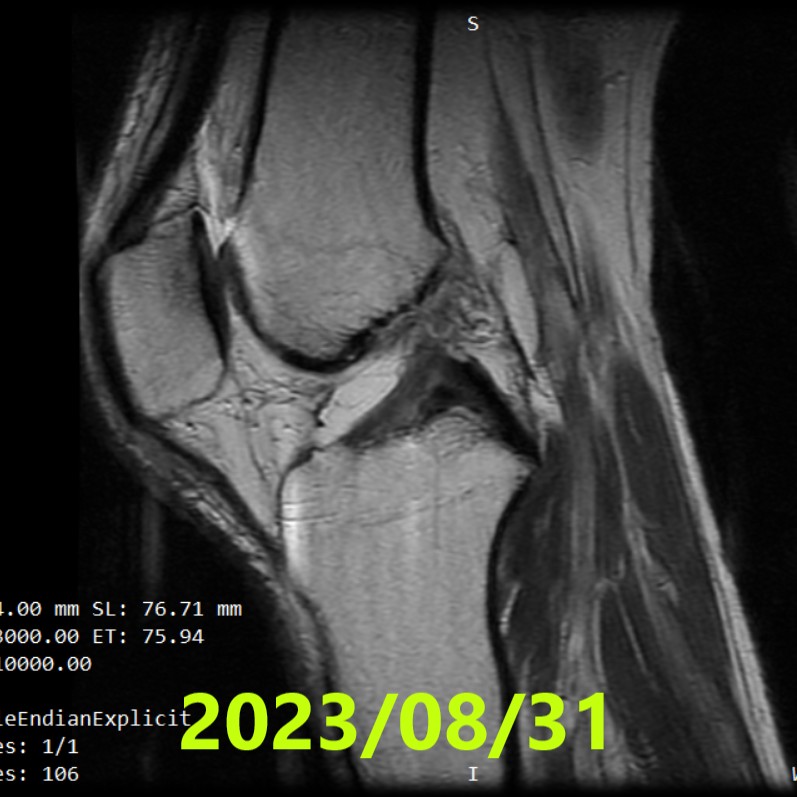

Seconda RM(~4 mesi)

- Data: 31 agosto 2023

- Lettura indipendente (3 radiologi): concorde ACLOAS grado 2(assottigliamento/allungamento con continuità preservata)

- Interpretazione: dal quadro complesso Ihara IV a reperti indicativi di continuità ripristinata

- RM #2(31/08/2023): ACLOAS 2 — continuità ripristinata